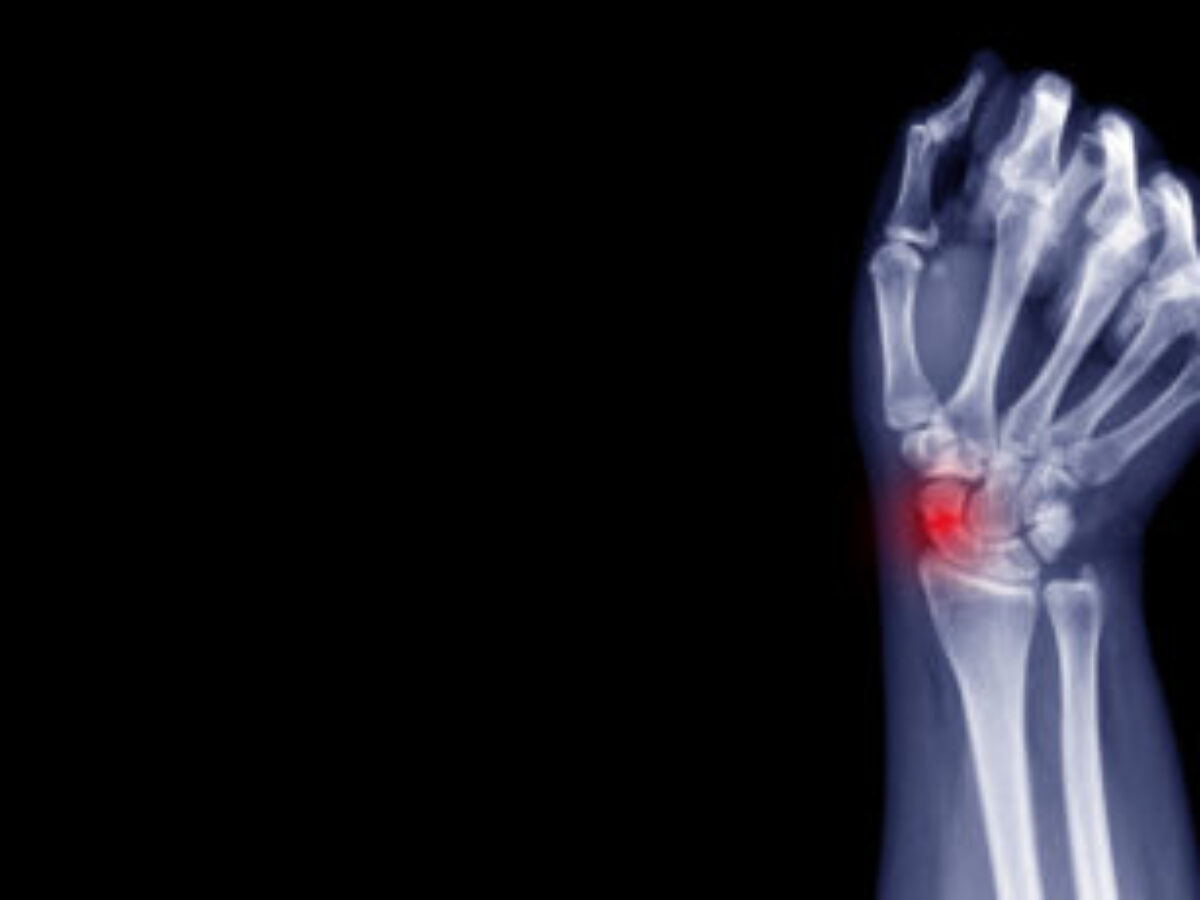

Hairline Fracture Symptoms Wrist. It is important to note that pain from a hairline fracture will often present as an ache with some sharp pain during activity. This is different from a more severe. Inability to move the wrist; The wrist hanging in an unnatural position The areas affected can be: Web the quick answer is the symptoms of hairline fractures of the wrist are pain (sharp or achy), swelling, bruising and lack of function of the wrist. It’s normal to have some discomfort in the areas around your fracture. A broken wrist might cause these signs and symptoms: Learn about the symptoms, causes, diagnosis, and treatment. Web symptoms of a wrist fracture include: Areas that have been immobilised Web if your wrist function hasn’t improved within 6 weeks of following this advice, it’s a good idea to talk to a healthcare professional about your symptoms. Web symptoms to watch for. Identifying a hairline fracture in the wrist might be tricky as the symptoms can be. Severe pain that might worsen when.

Identifying a hairline fracture in the wrist might be tricky as the symptoms can be. Areas that have been immobilised The wrist hanging in an unnatural position Learn about the symptoms, causes, diagnosis, and treatment. Web if your wrist function hasn’t improved within 6 weeks of following this advice, it’s a good idea to talk to a healthcare professional about your symptoms. Web the quick answer is the symptoms of hairline fractures of the wrist are pain (sharp or achy), swelling, bruising and lack of function of the wrist. Web a wrist hairline fracture occurs when there is a small break in one of the bones of the wrist. Web symptoms of a wrist fracture include: A broken wrist might cause these signs and symptoms: It’s normal to have some discomfort in the areas around your fracture.